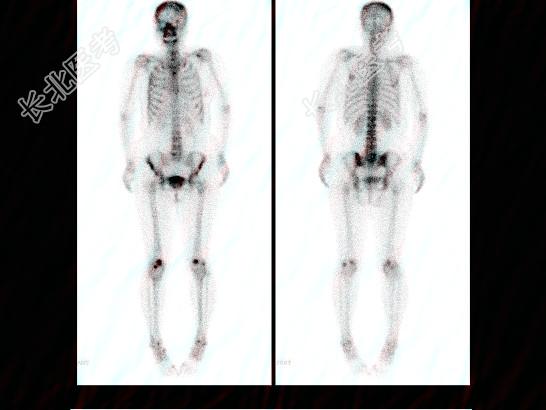

- 多项选择题右乳癌根治术后5年,无明显不适, 血清CA153正常,行全身骨显像如图, 可能的诊断是 ( )

A、多发骨转移瘤

B、腰椎退行性改变

C、大致正常的骨影像

D、腰4、5骨转移瘤

E、骨质疏松